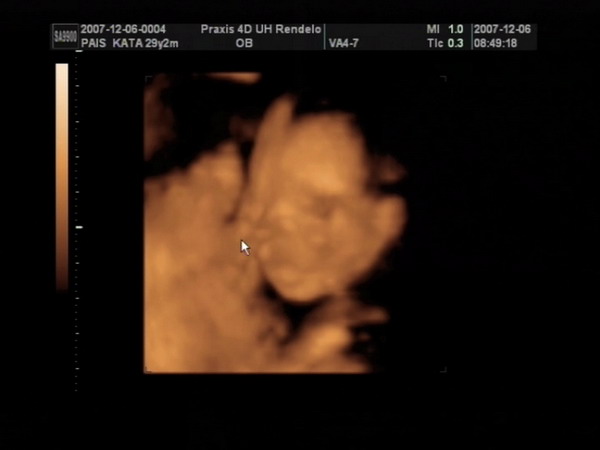

Végre sikerült olyan formátumot csinálni a 4D-s képeinkből, amit ide is fel tudok tenni, úgyhogy büszkén fel is teszem a fotókat :).

Na és az egyértelmű bizonyíték arra, hogy Csenge kiscsaj:

Kép

Meli, elméletileg a kiscsaj van alul, és felette a kisfickó - de ez nem 100%, mert dec. 6-án voltunk 4D-n, és azóta lehet, hogy megfordultak. Tegnap voltam dokinál, ő viszont már azt mondta, hogy a végleges helyükön vannak a törpék, már nincsen helyük megfordulni (az viszont nem látszott tegnap, hogy melyik van alul-felül). Mikuláskor kb. 35 dkg-ok voltak, tegnap csak a fejüket mérte a doki bácsi. Minden rendben van velük, de harántfekvéses mindkettő :roll: